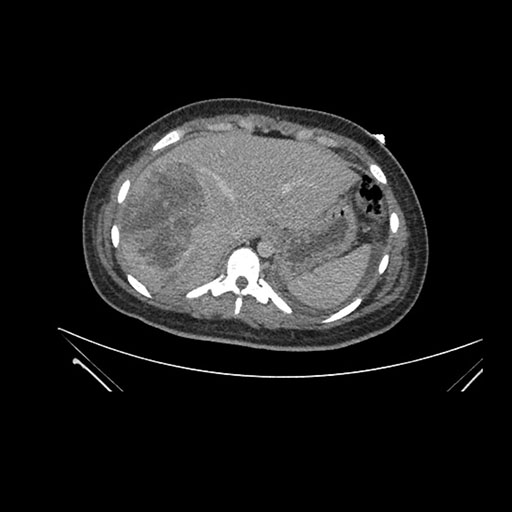

Imaging Analysis

Look through the patient's CT scan to identify any areas of concern for the necessary procedure.

Based on initial findings, which issue(s) would you be most concerned about?